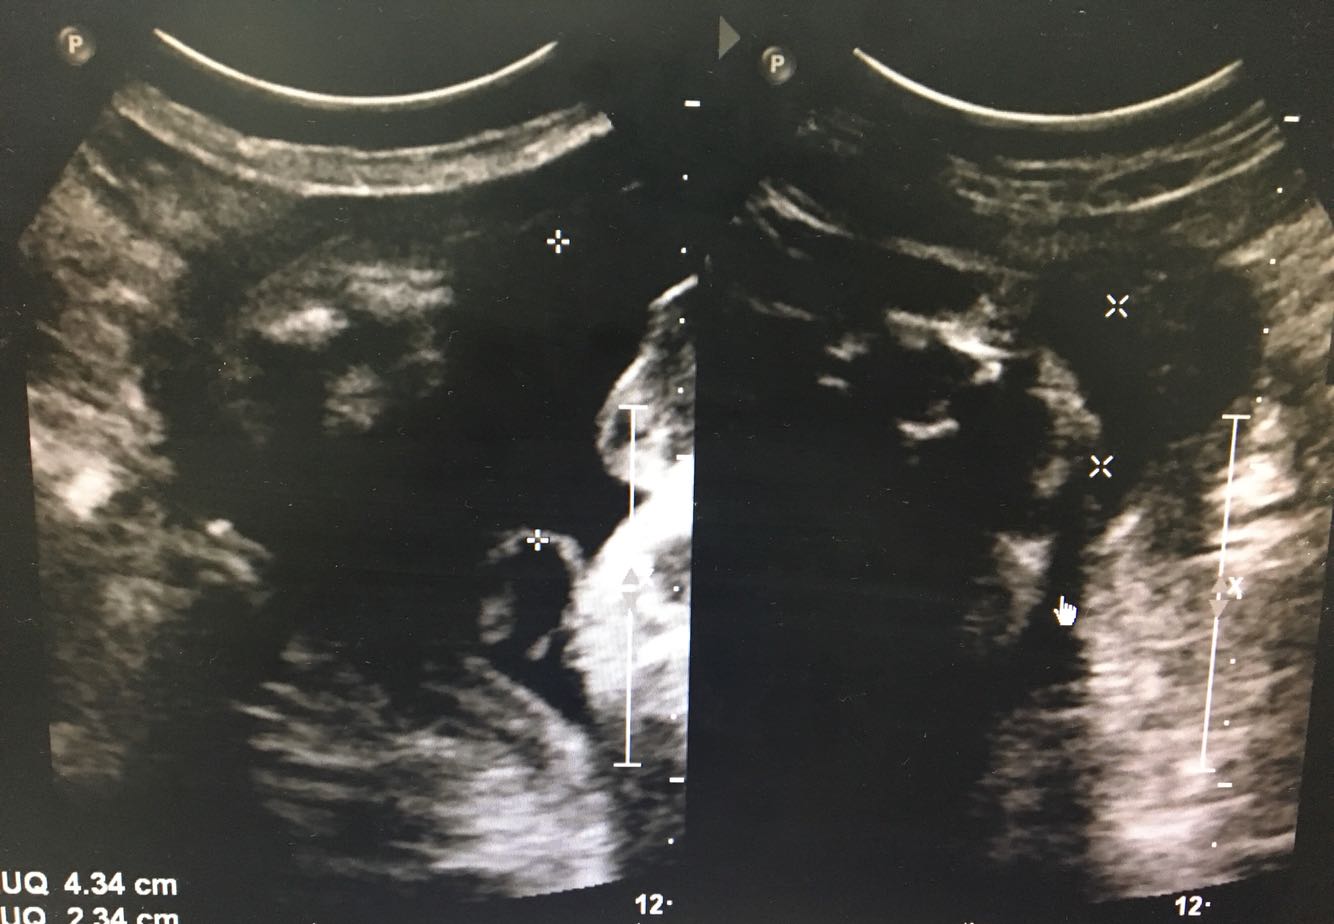

B超:胎头位于:耻上; 双顶径: 95 mm; 头围长: 339 mm; 腹围长: 327 mm; 股骨长: 75 mm; 肱骨长: 59 mm; 胎动胎心:佳(胎心率:143次/分); 胎盘附着于:宫体,前壁;分期:II期;胎盘厚度: 32 mm。 羊水指数: 43 、23 、51 、49 mm。 胎儿颈部未见脐血流信号。脐动脉血流 S/D 2.8 ,RI 0.65 。